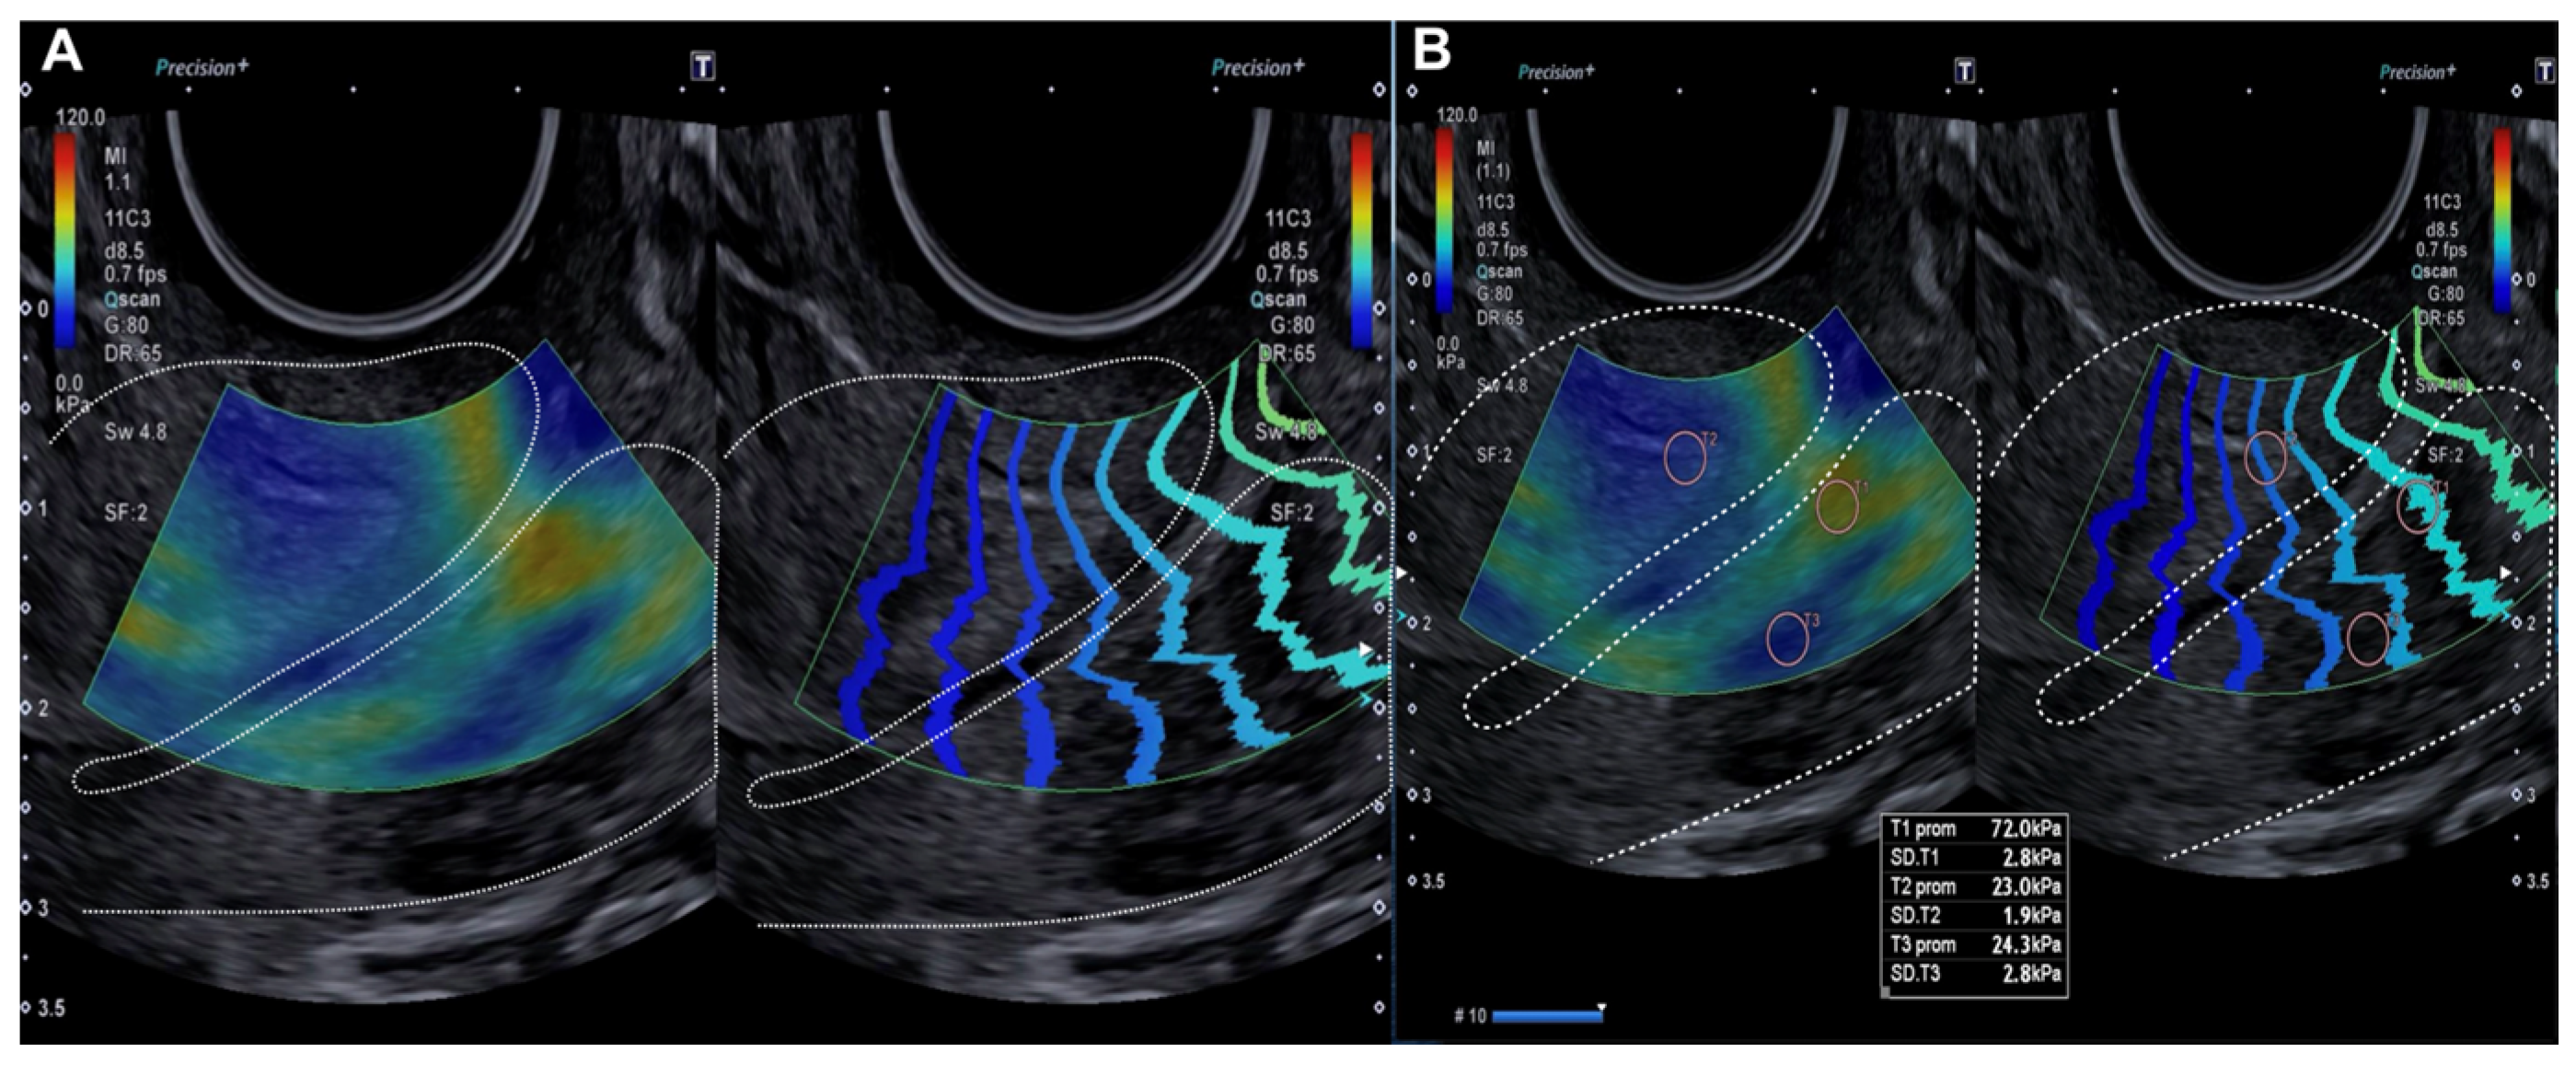

Figure 1.

Longitudinal assessment of the cervix (dotted line) by elastography (SonoElastoColposcopy). (A) A cervix with low stiffness (blue) and an adequate transmission wave control (in parallel). (B) Quantitative assessment of the stiffness measured in Kilopascals (Kpa).

The probe was subsequently rotated 90º and the external cervical os (ECO) was identified in the transverse section of the cervix using 2D ultrasound. In this transverse location of the ECO, elastography was reactivated and a new qualitative assessment was performed, identifying areas of increased stiffness (red color) (Figure 2). A quantitative assessment of the areas of increased (red) and decreased stiffness (blue) was then performed (Figure 2). Lastly, the locations of the lesions were described according to the model previously used in colposcopy.

Figure 2.

Transverse evaluation of the uterine cervix at the level of the OCE (dotted line) by elastography (SonoElastoColposcopy). (A) A cervix with low stiffness (blue) and an adequate transmission wave control (in parallel). (B) Quantitative assessment of the stiffness measured in Kilopascals (Kpa).